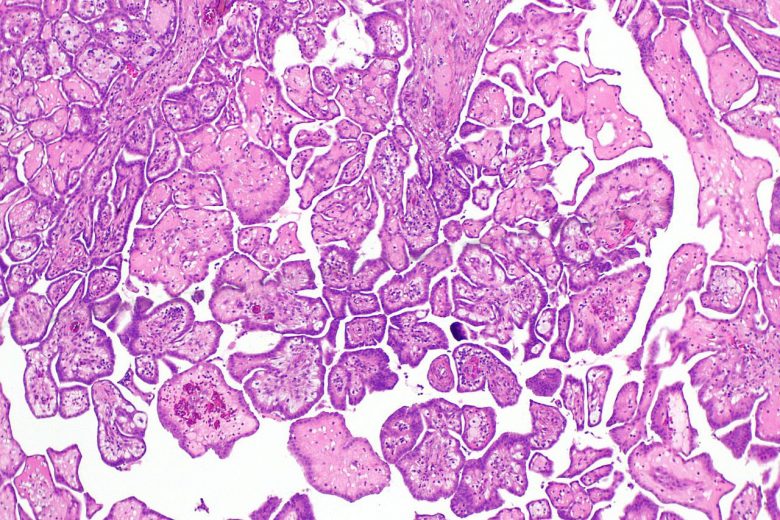

Gestational trophoblastic disease

“In gestational trophoblastic disease (GTD), a tumor develops inside the uterus from tissue that forms after conception (the joining of sperm and egg). This tissue is made of trophoblast cells and normally surrounds the fertilized egg in the uterus. Trophoblast cells help connect the fertilized egg to the wall of the uterus and form part of the placenta (the organ that passes nutrients from the mother to the fetus).

“Sometimes there is a problem with the fertilized egg and trophoblast cells. Instead of a healthy fetus developing, a tumor forms. Until there are signs or symptoms of the tumor, the pregnancy will seem like a normal pregnancy.”

More facts about GTD:

- Hydatidiform mole (HM) is the most common type of GTD.

- Gestational trophoblastic neoplasia (GTN) is a type of gestational trophoblastic disease (GTD) that is almost always malignant.

- Age and a previous molar pregnancy affect the risk of GTD.

- Signs of GTD include abnormal vaginal bleeding and a uterus that is larger than normal.

- Tests that examine the uterus are used to detect (find) and diagnose gestational trophoblastic disease.

Image Credit: Nephron / Wikimedia Commons.